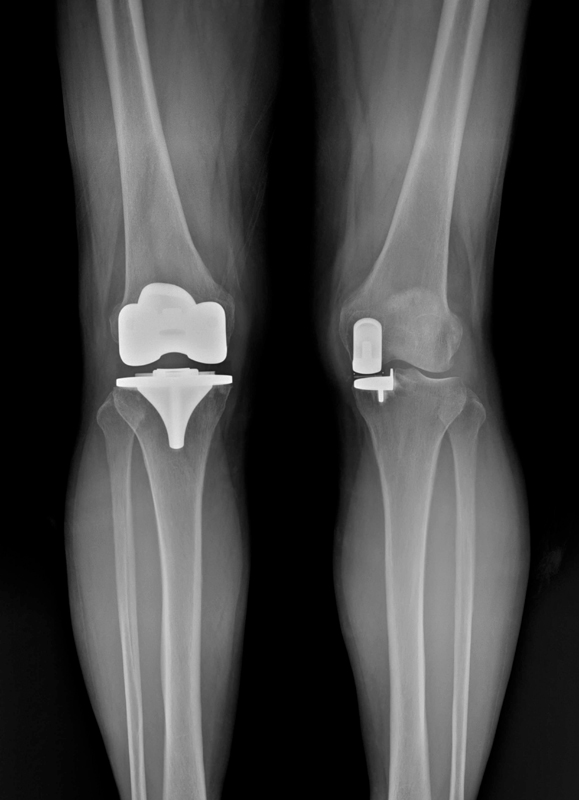

무릎 관절염이 진행되면 연골이 닳고, 뼈끼리 부딪히며 통증이 생깁니다. 이때 손상된 관절면을

인공관절로 바꿔 통증을 줄이고 보행 기능을 회복시키는 수술이 인공관절 치환술입니다.

하지만 인공관절 수술은 한 가지가 아닙니다. 손상 범위가 어디까지인지에 따라

‘전치환술’과 ‘반치환술’로 나뉘며, 아산재건은 이 구분을 가장 중요하게 봅니다.

무조건적인 전체 수술은 권하지 않습니다.

살릴 수 있는 연골이 있다면 ‘반치환술’로

회복 부담을 낮추고, 변형이 심하다면 ‘전치환술’로 확실하게 교정합니다. 환자에게 가장 이득이 되는 방식을 명의의 눈으로 찾아냅니다.